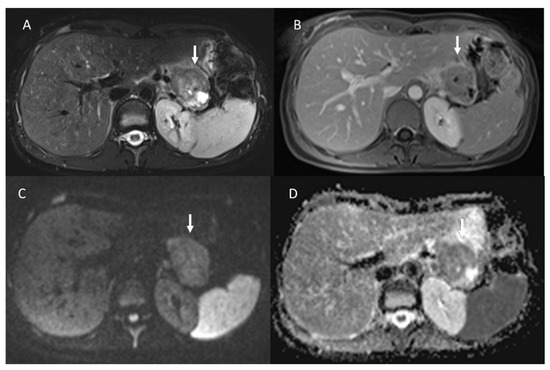

Figure 1.

Portal CT evaluation of small bowel NEN (arrow in (A)): intraluminal enhanced polypoid lesion (arrow) with desmoplastic reaction (arrow in (B)).

Figure 2.

CT evaluation during portal phase of pancreatic NEN ((A): arrow) with liver metastasis ((B): arrow).